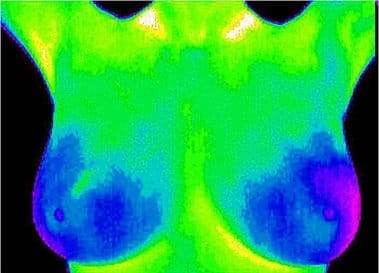

La otra conferencia ‘Salud de la Mama’ será el 27 de enero a las 19h en inglés y el 10 de febrero a las 20h en castellano. Se trata de una charla sobre la salud de la mama y cómo cuidarlas por Liz Nagle, terapeuta natural y terapeuta de biomagnetismo. Liz también hablará sobre el escáner con termografía, un método de detección y monitoreo eficaz, no invasivo y rápido.